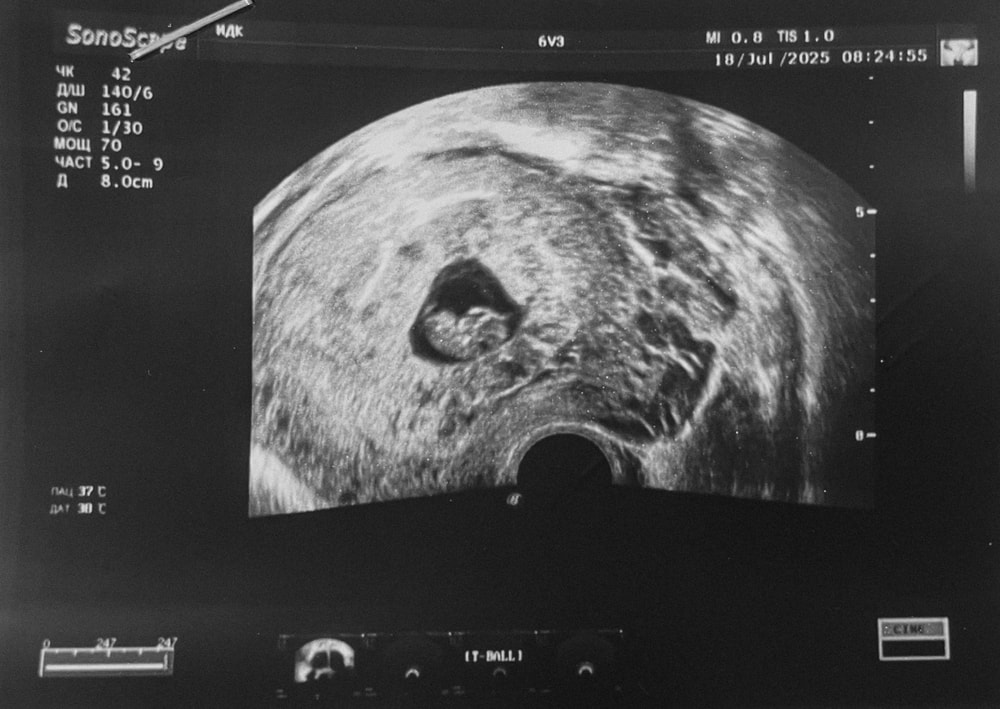

Мама девочки (2 года), жду мальчика, 11 неделя

8 недель 3 дня 🫶🏼

КТР 19.8 мм

ЖМ 4.7 мм

СВДПЯ 25 мм

Кольцевидный хорион.

Шейка 37 мм.

А вам про размер пя ничего не сказали ?

Ирина ツ, вот сказали. Предыдущий пост у меня. Циркулярное расположение хориона или кольцевидный хорион. Свободного места в ПЯ всего 25 мм, все плодное яйцо не измеряли.

Все плохо?

Алина, кольцевидный хорион это норма для срока,а вот пя маленькое для такого эмбриона,сама сталкивалась, поэтому обращаю внимание на размеры пя по соотношению к ктр,это не очень хорошо,мало места там и часто заканчивается печально,но я не утверждаю что 100% может вам и померяли неправильно его,хотя по фото места мало